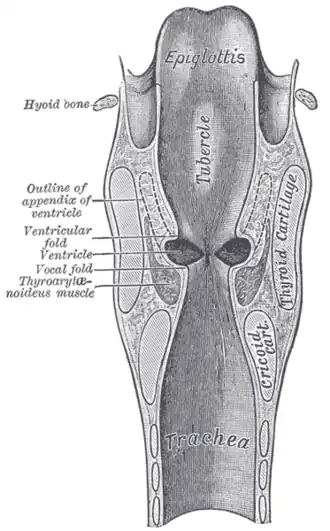

Additional images

-

Vocal folds.

Vocal folds. -